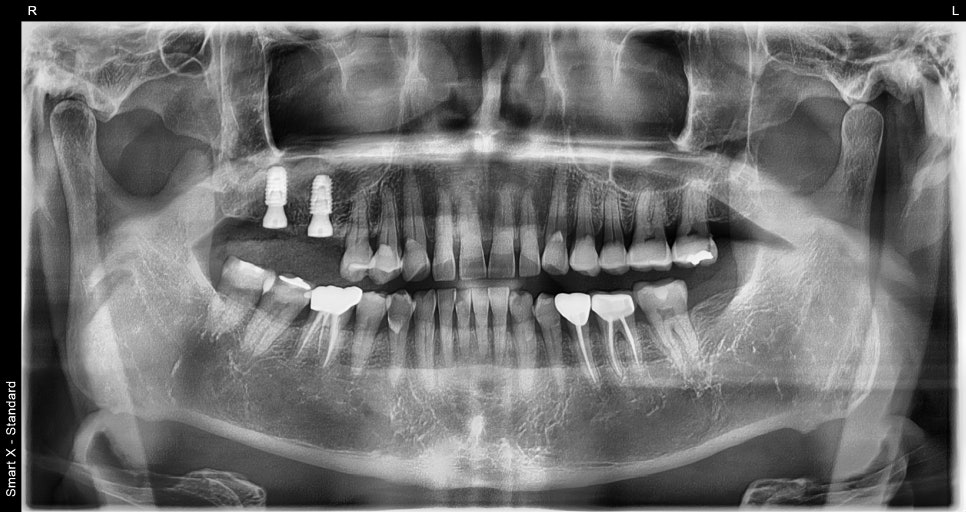

At the follow-up visit, panoramic imaging confirmed that the implant was settling in well.

Custom abutment fabrication

The final stage of an implant is the prosthesis (crown).

It was custom-made at the in-house dental lab based on scan data, and after placement, photographs were used to check the fit between the gums and the prosthesis again.